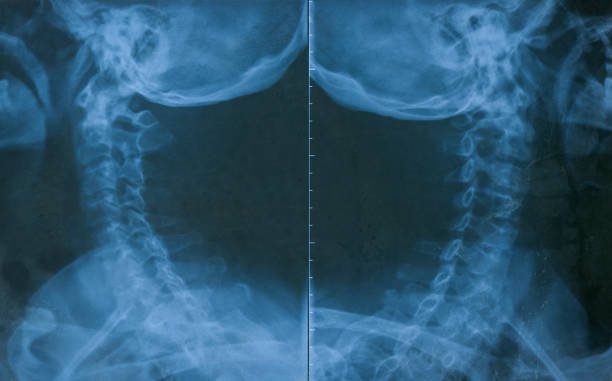

천식은 기관지의 염증과 경련으로 인해 기침, 숨이 차고 가슴이 답답한 등의 호흡곤란 증상을 보이는 만성적인 폐질환입니다. 이러한 천식 환자들은 종종 목이 간질간질하고 마른 기침이 나타날 수 있습니다.

천식의 원인은 다양하지만, 대개는 호흡기에 접촉한 알레르기성 물질이나 공기 오염 물질에 대한 반응으로 인한 것입니다. 이러한 반응으로 인해 호흡기의 기관지가 수축하고 염증이 생겨 호흡 곤란 증상이 나타납니다. 이때, 기침은 호흡기를 청소하고 비염, 기관지염 등으로 인한 분비물을 제거하는 역할을 합니다.

하지만, 천식 환자의 경우 호흡기의 염증과 경련으로 인해 기침이 잘 제어되지 않아 목이 간질간질하고 마른 기침이 나타나게 됩니다. 또한, 천식 환자는 호흡 곤란으로 인해 호흡을 하려고 할 때 공기가 막혀 기침을 유발할 수 있습니다. 따라서, 천식 환자가 목이 간질간질하고 마른 기침이 나타날 경우 즉각적인 치료가 필요합니다. 천식은 약물 치료와 호흡 운동 치료 등으로 적극적으로 치료가 가능하며, 적절한 치료로 호흡기 증상을 완화시킬 수 있습니다.